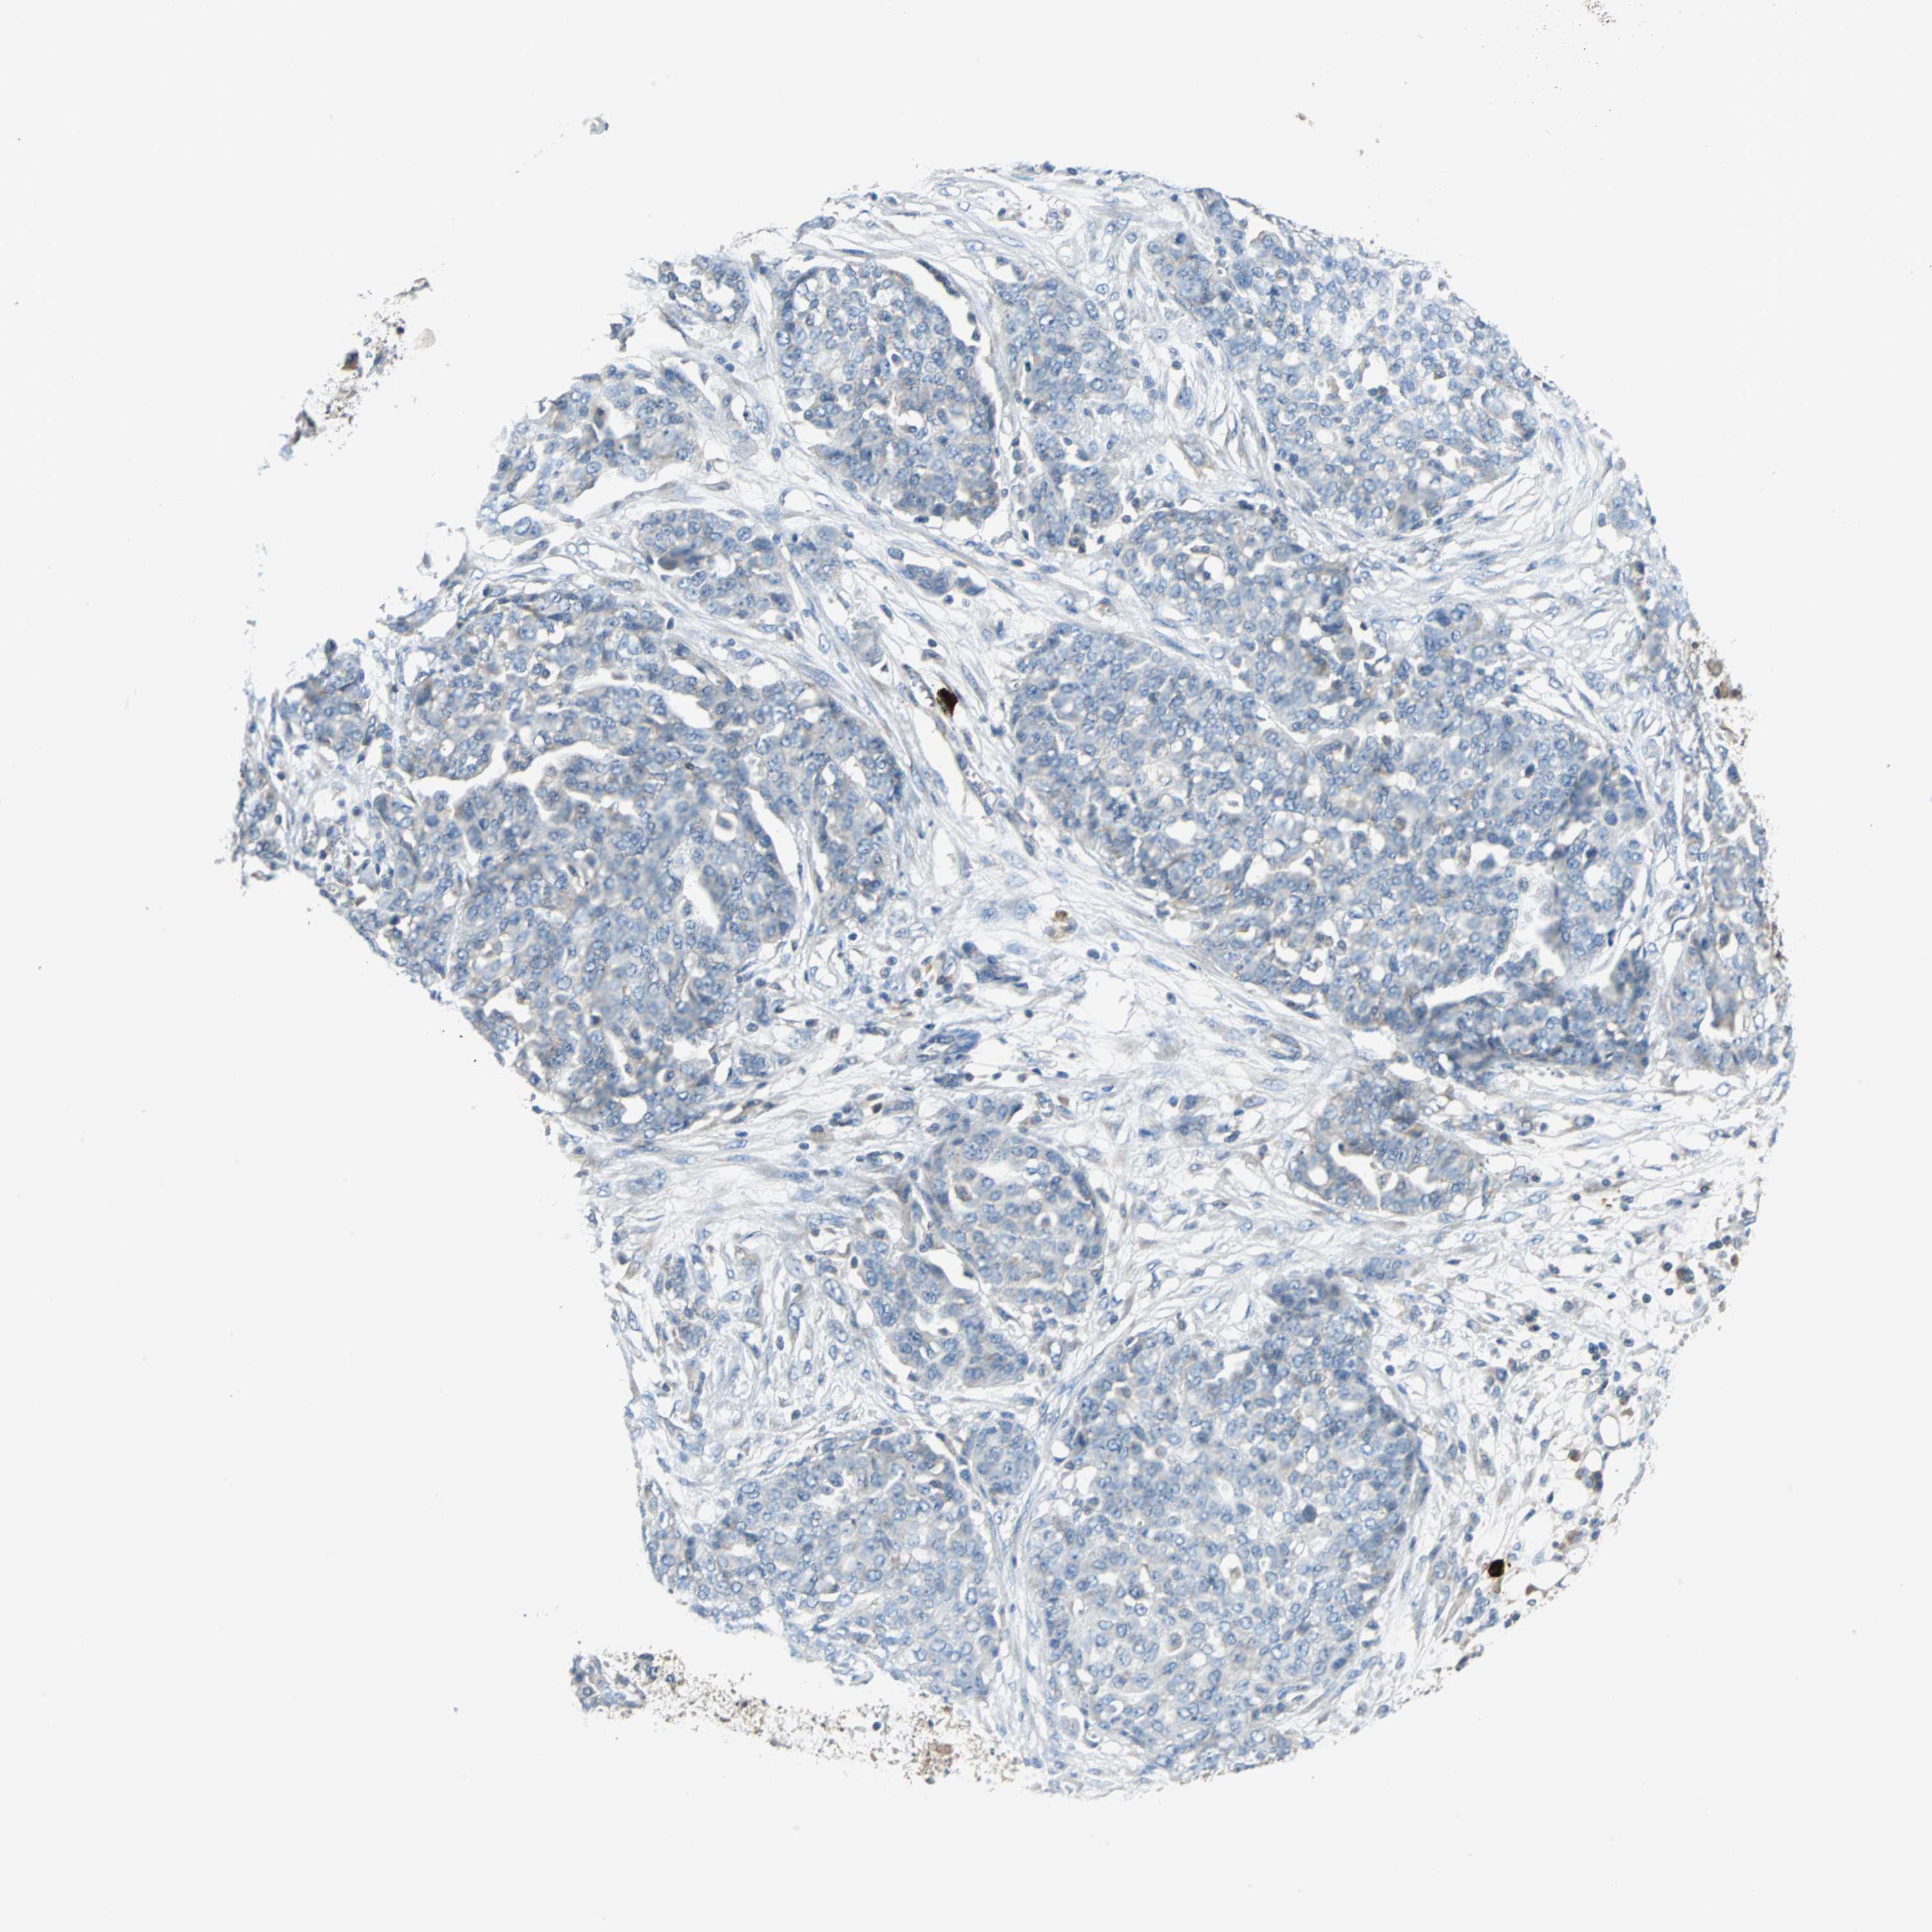

OVARIAN CANCER - Protein expressioni

A mouse-over function shows sample information and annotation data. Click on an image to view it in a full screen mode. Samples can be filtered based on level of antibody staining by selecting one or several of the following categories: high, medium, low and not detected. The assay and annotation is described here.

Note that samples used for immunohistochemistry by the Human Protein Atlas do not correspond to samples in the TCGA dataset.

Antibody stainingi

Antibody staining in the annotated cell types in the current human tissue is reported as not detected, low, medium, or high, based on conventional immunohistochemistry profiling in selected tissues. This score is based on the combination of the staining intensity and fraction of stained cells.

Each image is clickable and will lead to virtual microscopy that enables deeper exploration of all samples and also displays staining intensity scores, fraction scores and subcellular localization as well as patient and tissue information for each sample.

Antibody HPA006479

Antibody HPA008689

Antibody CAB020712

Cystadenocarcinoma, serous, NOS